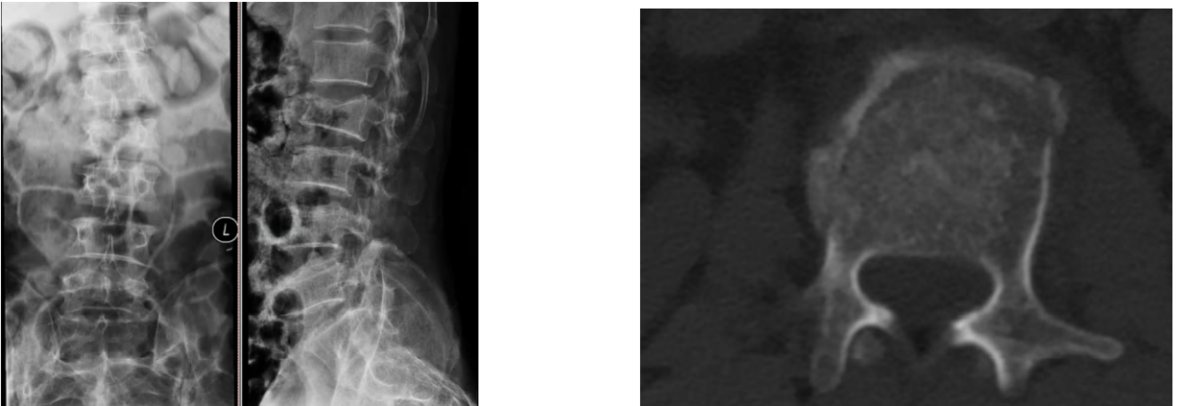

病例1 坠落伤,无神经症状

AO分型

- 分型:A1型

- 神经功能障碍分级:N0

- 修正参数:

- AO补充评分:A1+N0(1+0) 1分

TLICS评分

- 压缩型骨折(1分)

- 无神经损伤 (0分)

- PLC无断裂(0分)

- 1分

载荷评分

- 碎裂小于30% 1分

- 后凸4~9度 2分

- 移位0~1mm 1分

- 4分

治疗方案:非手术治疗